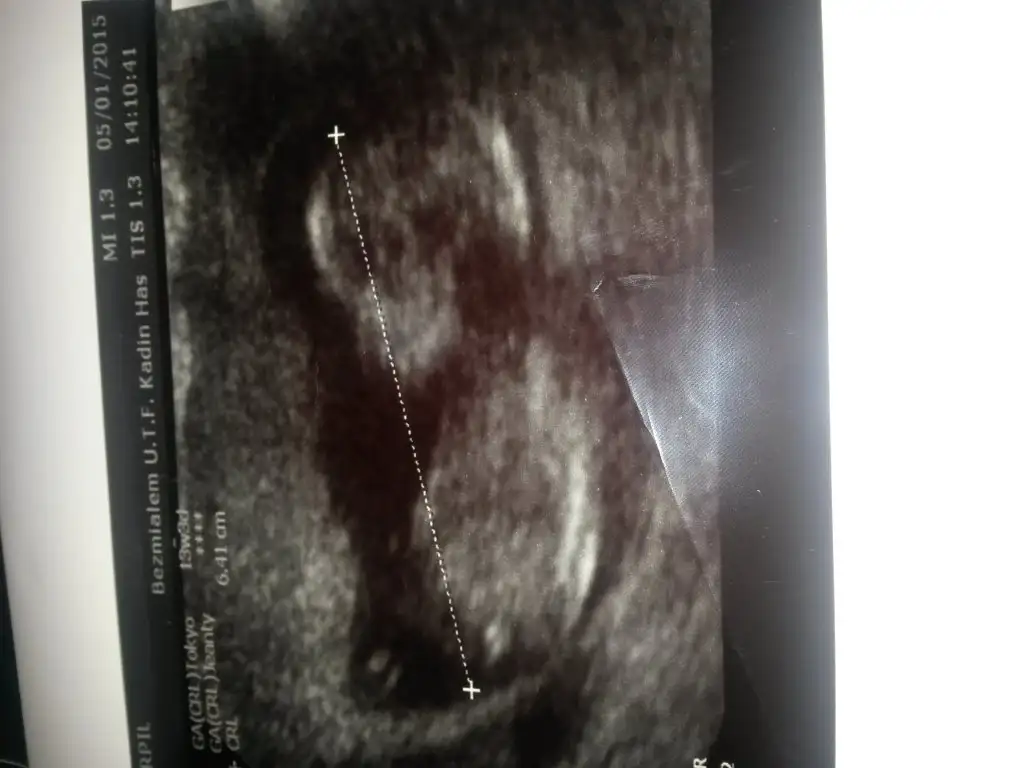

10 hafta çok erken tahmin için cnm ya eğer bu fotoya 13 hafat deseydin erkek derdim ama 10 haftada nublar nerdeyse aynı oluyo bence

Ne bileyim kuzum onceden erkek denildi dediysen emin olmak icin demistr belki dun ne demisti dr sana pekiAma anlamadım yaa 100/99 kız dedi bı hafta sonra gel kesinleştırelim dedi bu ne şimdi![]()

canım ben dun gıtmedimki bugun gıttım doktora 100/99 diyo sonra emin olamıyoDünkü Dr ne demişti peki bende nubinu koza benzetmiştir senin bikizinmj vardi canim Dr net goremediyse insanda öyleddemiştir belki